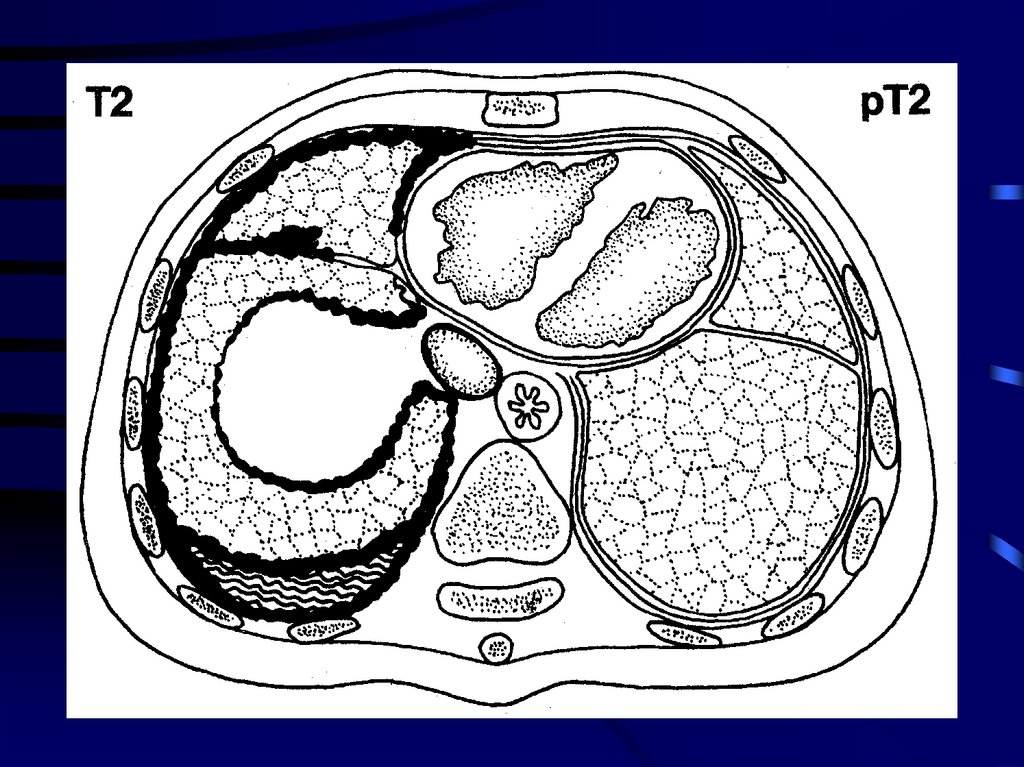

10.

11.

• Опухоль распространяется на любой из следующих

органов: легкое на стороне поражения,

внутригрудную фасцию, диафрагму, перикард.

12.